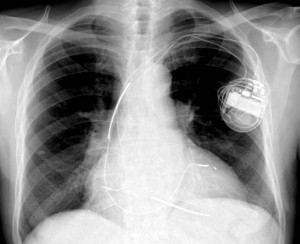

1) Telemedizinische Überwachung von Implantaten zur kardialen Defibrillations- / Resynchronisationstherapie (ICD / CRT)

Ein nicht unwesentlicher Teil kardiologischer Patienten lebt mit einem chronisch implantierten elektronischen Geräte zur Behandlung von Herzrhythmusstörungen. Die verwendeten Implantate arbeiten generell mit hoher Zuverlässigkeit, doch Ihre Funktion kann im Einzelfall durch verschiedene Faktoren gestört werden. Entsprechende Funktionsstörungen können im ungünstigsten Fall zu schmerzhaften ICD-Schockentladungen, bedrohlichen Rhythmusstörungen oder anderen unerwünschten Ereignissen führen. Klinische Studien haben gezeigt, dass die kontinuierliche telemedizinische Überwachung des Implantates zur frühzeitigen Erkennung von Funktionsstörungen und zu einer Reduktion unerwünschter klinischer Ereignisse führt. Zudem können Rhythmusstörungen zeitiger diagnostiziert und behandelt werden.

Im HGZ werden daher seit vielen Jahren die betreuten Patienten mit implantiertem ICD- oder CRT-System telemedizinisch angebunden und überwacht.